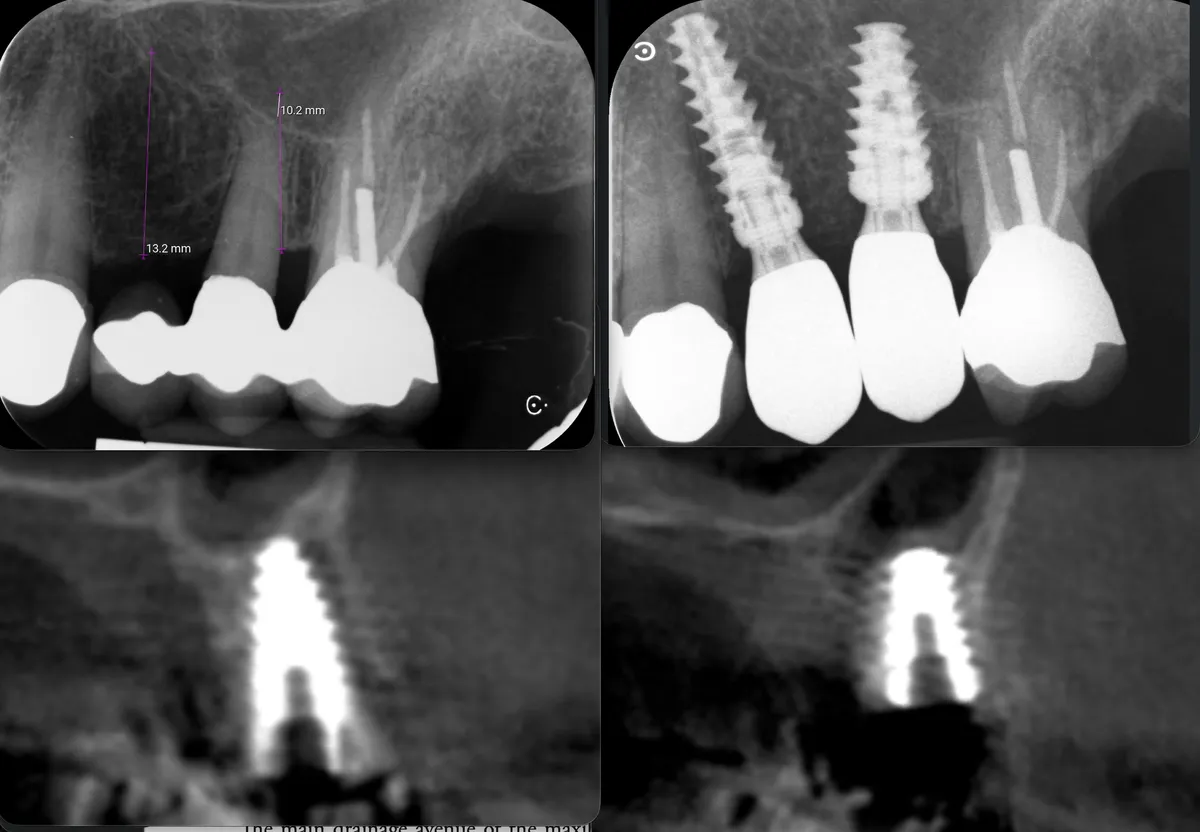

Caso clinico: espansione crestale ERE con impianto immediato e rigenerazione simultanea. Da ponte fallito a impianto in un'unica seduta.